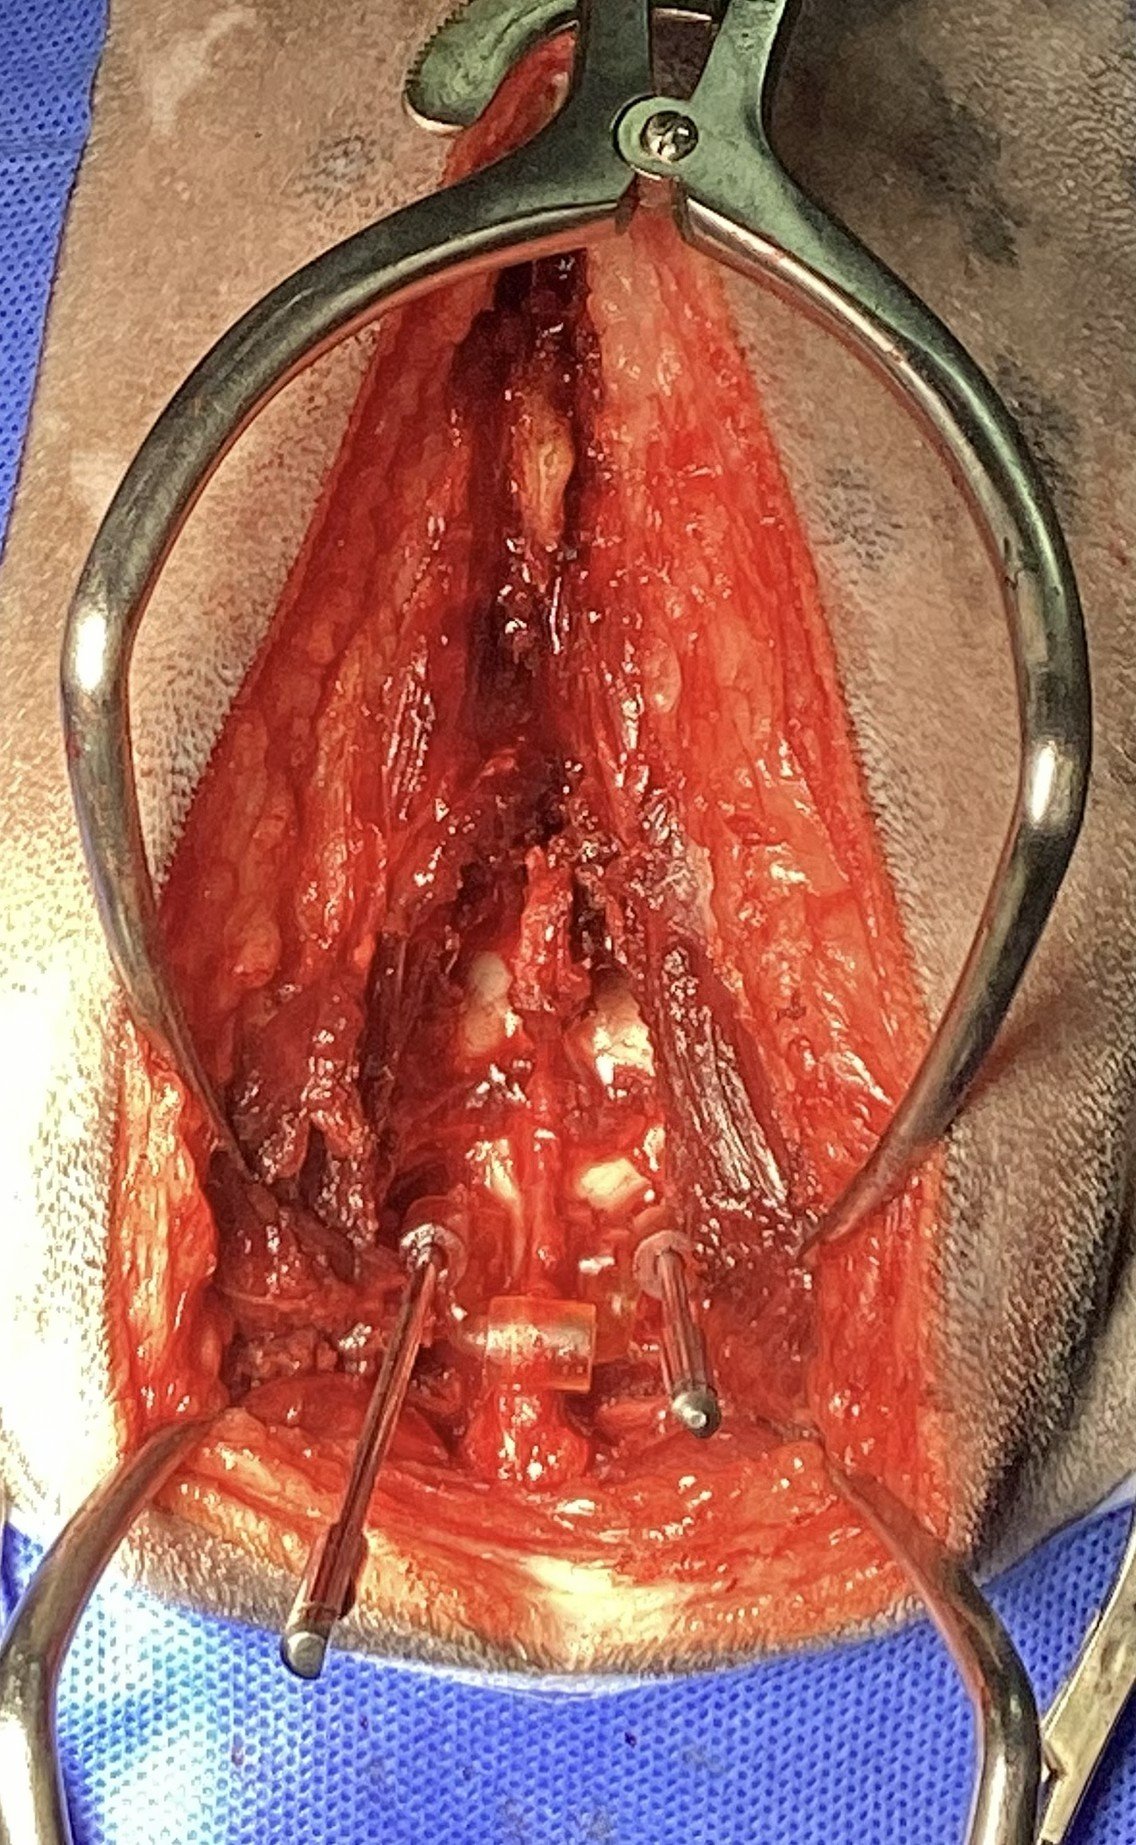

Example 1: Lumbosacral distraction and stabilisation

Example 2: Segmental stabilisation for subarachnoid diverticulum